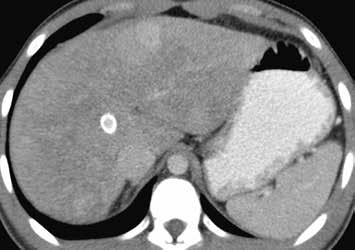

Nativně na CT je nezřetelně naznačeno několik hypodenzních ložisek (17). Všechna se vcelku homogenně sytí v arteriální fázi (18). V portovenózní fázi je sycení jater celkově nehomogenní, ložiska jsou však nadále lehce hyperdenzní oproti okolnímu parenchymu jater (19).